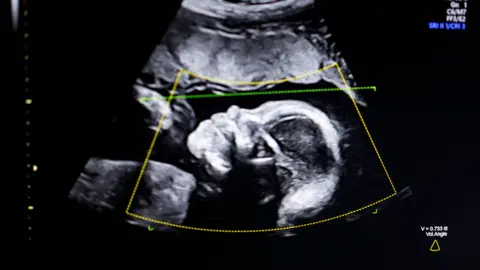

Getty Images An image of a baby's head shown on screen on an ultrasound scan. It is a grainy black-and-white image of the side of the head. You can clearly see the nose and eyes. Overlaid on the top of the image are data from the imaging machine including a yellow box and a green dotted line.Getty Images

Private clinics often offer reassurance or sexing scans before the standard NHS anomaly scan which is normally offered between 18 and 21 weeks into the pregnancy